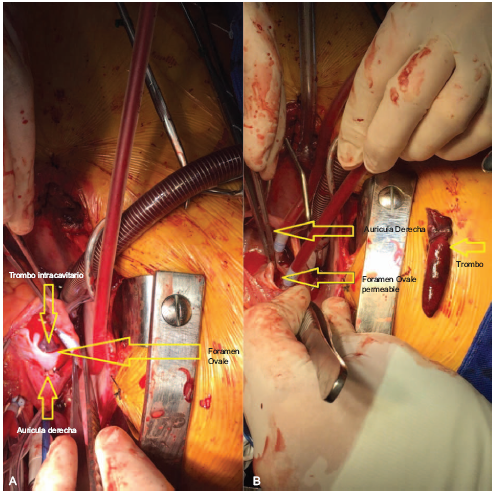

En urgencias, se sospechó tromboembolismo pulmonar (TEP), confirmandose por ecocadiograma transtoracico, el foramen oval evidencio ecodensidad cilíndrica de 60 mm de longitud y 14 mm de diámetro pasando activamente por el foramen (trombo cabalgado) con al menos 30mm de esta estructura ya ubicados en la aurícula izquierda, ver Tabla 1 y Figura 1. Adicionalmente, con miembro inferior izquierdo asimétrico, confirmándose por dopler, trombosis venosa profunda (TVP) poplítea izquierda. Cirugía Cardiovascular realiza trombectomia y cierre foramen ovale con tiempo quirúrgico de 180 minutos (min), bajo circulación extracorpórea de 71 min y clamp de 47 min. Cardioplejia sanguínea. Monitoreo hemodinámico invasivo y catéter arteria pulmonar. Sangrado 500cc. Temperatura 34°C. Se inició óxido nítrico por hipertensión pulmonar supra sistémica, ver Tabla 2. Hallazgos quinirgicos, un gran trombo de 50mm longitud por 10mm ancho, el 80% del mismo se alojaba en aurícula izquierda, anclado al septum pasando a través del foramen ovale, ver Figura 2. Se monitoriza bienestar fetal con doppler continuo. Al ingreso a UCI, paciente con soporte ventila-torio, vasopresor, inotrópico e inodilatador. Fetocardia 120 latidos/minuto, llenado capilar mayor a 4 segundos. 48 horas después, se confirma por ecografía la ausencia de fetocardia. Después de 18 horas, durante el parto presenta un sangrado de 2000 ml, se activa el código rojo, manejo con cristaloides, transfusión de 4 unidades glóbulos rojos y colocación de balón uterino de Bakri para taponamiento uterino, igualmente se administra oxitocina, metilegono-vina y misiprostol 400 mg intrarectal. Al cabo de 48 horas, se retira balón uterino. Evolución favorable en su perfil hemodinámico y gasimétrico, permitiendo el retiro del soporte multisistémico ver Tabla 2. La estrategia ventilatoria invasiva se desarrolló con éxito por 5 días utilizando un modo ventilatorio asistido controlado, presión positiva al final de la inspiración (PEEP) de 8, con fracciones inspiradas de oxigeno altas (100%) durante las primeras 24 hrs con utilización de óxido nítrico.

Figura 2 Trombointracavitario. A. Se observa el foramen ovale con el trombo intracavitario (vista auricula derecha) B. Se observa el trombo intracavitario y el foramen ovale.